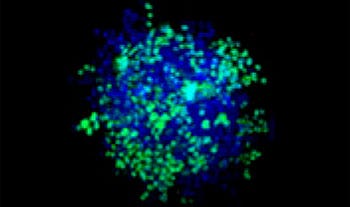

Making the spheroids transparent and imaging them with an FV3000 confocal laser scanning microscope enabled us to image the co-cultured cancer spheroids at depth. Staurosporine treatment increased the number of dead cells in a dose-dependent manner (Fig. 2*1). Three-dimensional analysis is required to determine which cells are dead and how many dead cells there are in a three-dimensional mass.

Figure 2. Drug response in co-culture spheroids

Figure 2. Drug response in co-culture spheroids*1